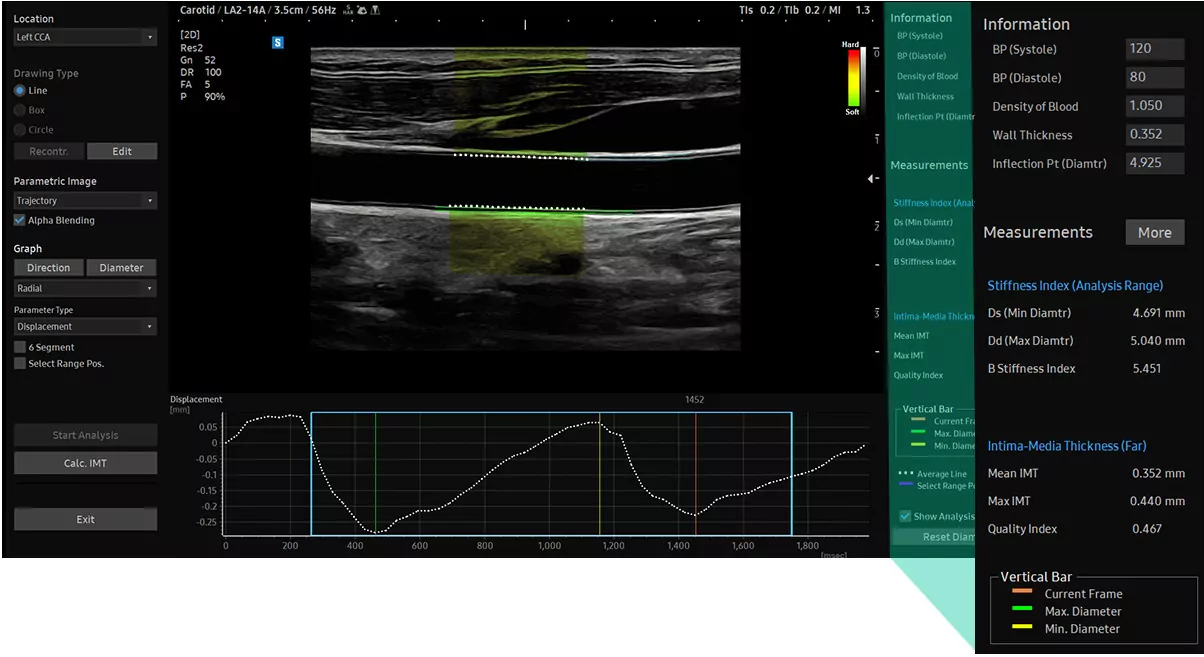

Arterial Analysis™ виявляє функціональні змінисудин, що забезпечує вимірювання таких значень, як жорсткість, товщина інтими-медіа та швидкість пульсової хвилі загальної сонної артерії. Оскільки функціональні зміни відбуваються перед морфологічними, ця технологія підтримує раннє виявлення серцево-судинних захворювань.

Артеріальний аналіз